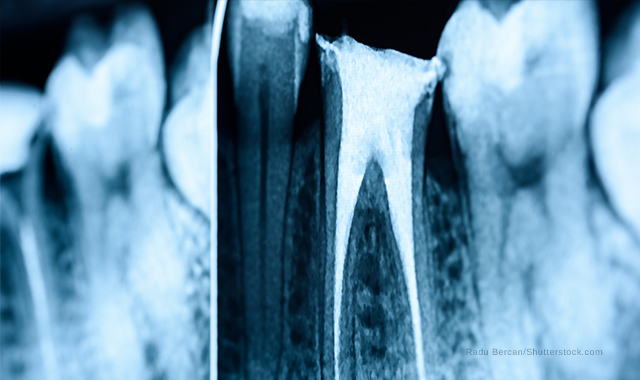

Radiopacity of the post

Posts that can be seen clearly in X-rays are easier to control, enabling the creation of better post positions. The new 3M™ RelyX™ Fiber Post 3D Glass Fiber Post offers excellent radiopacity.